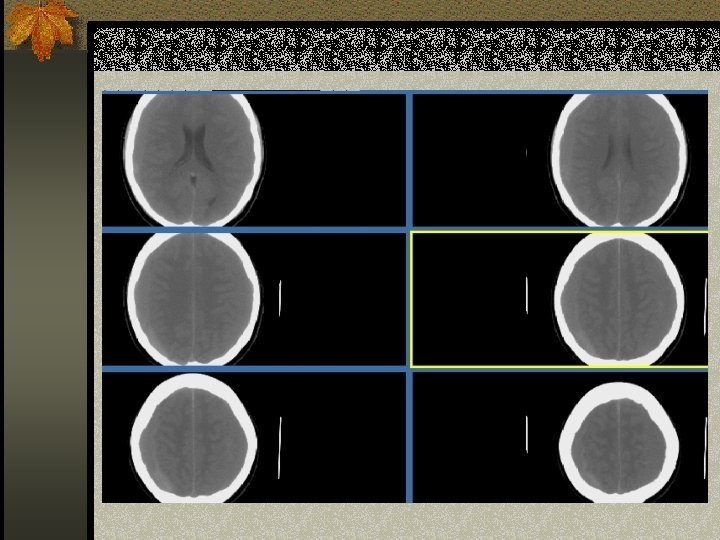

SUBDURAL HEMATOMA n Timbul antara dura dan arachnoid n Dapat melewati sutura n Timbul akibat disrupsi bridging cortical veins n Bentuk konkaf n Hipodens(hiperakut, kronis), isodens(subakut), hiperdens(akut)

W=33 L=41

PENANGANAN SDH n SDH akut dengan ketebalan > 10 mm atau pergeseran midline > 5 mm harus dievakuasi n Pasien yang koma dengan penurunan GCS >2 poin dengan SDH harus menjalani operasi evakuasi